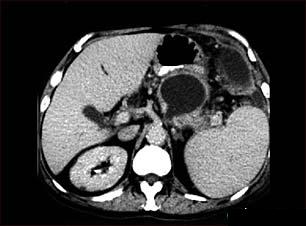

Abcesul pancreatic